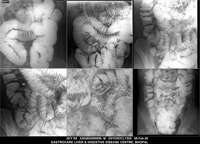

Section: ENTEROCLYSIS Total: 205 images

BaM Enteroclysis Loopogram BaE Fistulogram Urethrogram HSG